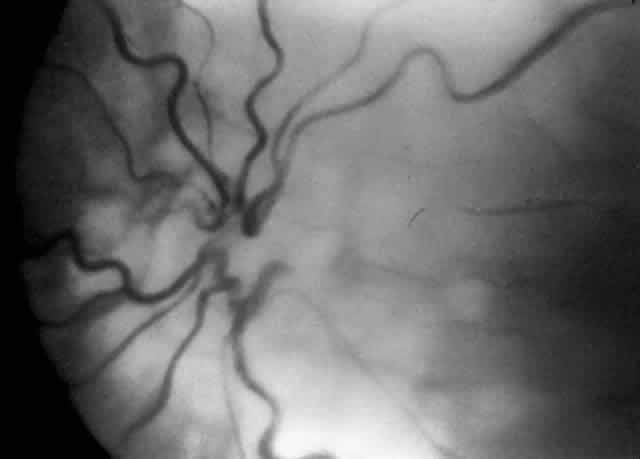

| Congenital retinoschisis is an inherited retinal disease characterized

by abnormal Müller's cell pillars that allow schisis cavities

to form. These schisis cavities are often described as being present 100% of

the time in the foveal area and 50% of the time in the far periphery. They

often result in decreased visual acuity by the third decade

of life. They certainly can result in reduced visual acuity much sooner

than that and may be present either at birth or during the first

decade of life. We believe that congenital retinoschisis is aggravated by vitreoretinal traction and have suggested that surgical therapy may be indicated for congenital retinoschisis under certain specific clinical settings:

The suggested treatment is scleral buckling or vitreous surgery, including removal of the inner wall of the schisis cavity with extensive panretinal photocoagulation to protect against rhegmatogenous retinal detachment.36–38 The hallmark of this tractional detachment is visual field changes that are larger than expected relative to the schisis cavity.36 Previously, demarcation lines resulting from full-thickness retinal detachment have been reported posterior to the schisis cavity.39 Others have considered this finding to represent an undetected rhegmatogenous retinal detachment, but based on observations during surgery, we believe that this detachment can be reversible and is tractional in origin (Fig. 6).36

COATS' DISEASE Coats' disease is an example of a vitreoretinal congenital vascular disease in which vitreous traction often plays a role leading to both preretinal and subretinal hemorrhage with resultant retinal detachment. Children with Coats' disease have been managed with vitreous surgery, scleral buckling, trans-scleral diathermy, cryotherapy, laser therapy alone, and laser therapy accompanied by injectable dyes (Fig. 7).40–42 Many different techniques have been employed because frequently neither the vessel abnormalities nor the vitreous traction can be resolved completely. With the possible advent of enzymatic surgery, such as use of plasmin or chondroitinase, it is hoped that a cleaner and more complete reduction of vitreoretinal traction will help advance the involution of these abnormal vessels without concurrent vitreous or subretinal hemorrhage.43